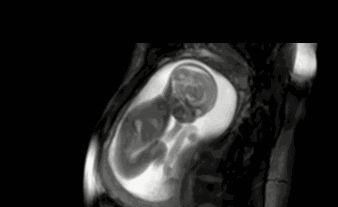

文章插图

比较明显的胎动在孕期32周,这个时候宝宝的一举一动更有力量,体现在胎动上也就更加明显。所谓胎动实际上就是胎儿在子宫里活动并碰到子宫壁。它代表胎儿的活力,从侧面证明了发育的情况。胎动太频繁或者长时间都不胎动,很有可能就是胎儿出现了问题。而规律的胎动代表着胎儿发育良好且比较聪明。

如果胎动能达到每两个小时6-10次胎动,就说明胎动很规律。2、孕妈情绪稳定在女性怀孕期间,孕妈的状态和胎儿息息相关。在这段时间,孕妇的情绪是否稳定,也说明了胎儿的状态。如果孕妈情绪大起大伏,经常处于低落、精神不振的状态,那么胎儿在子宫内的适应状况也不是很好。